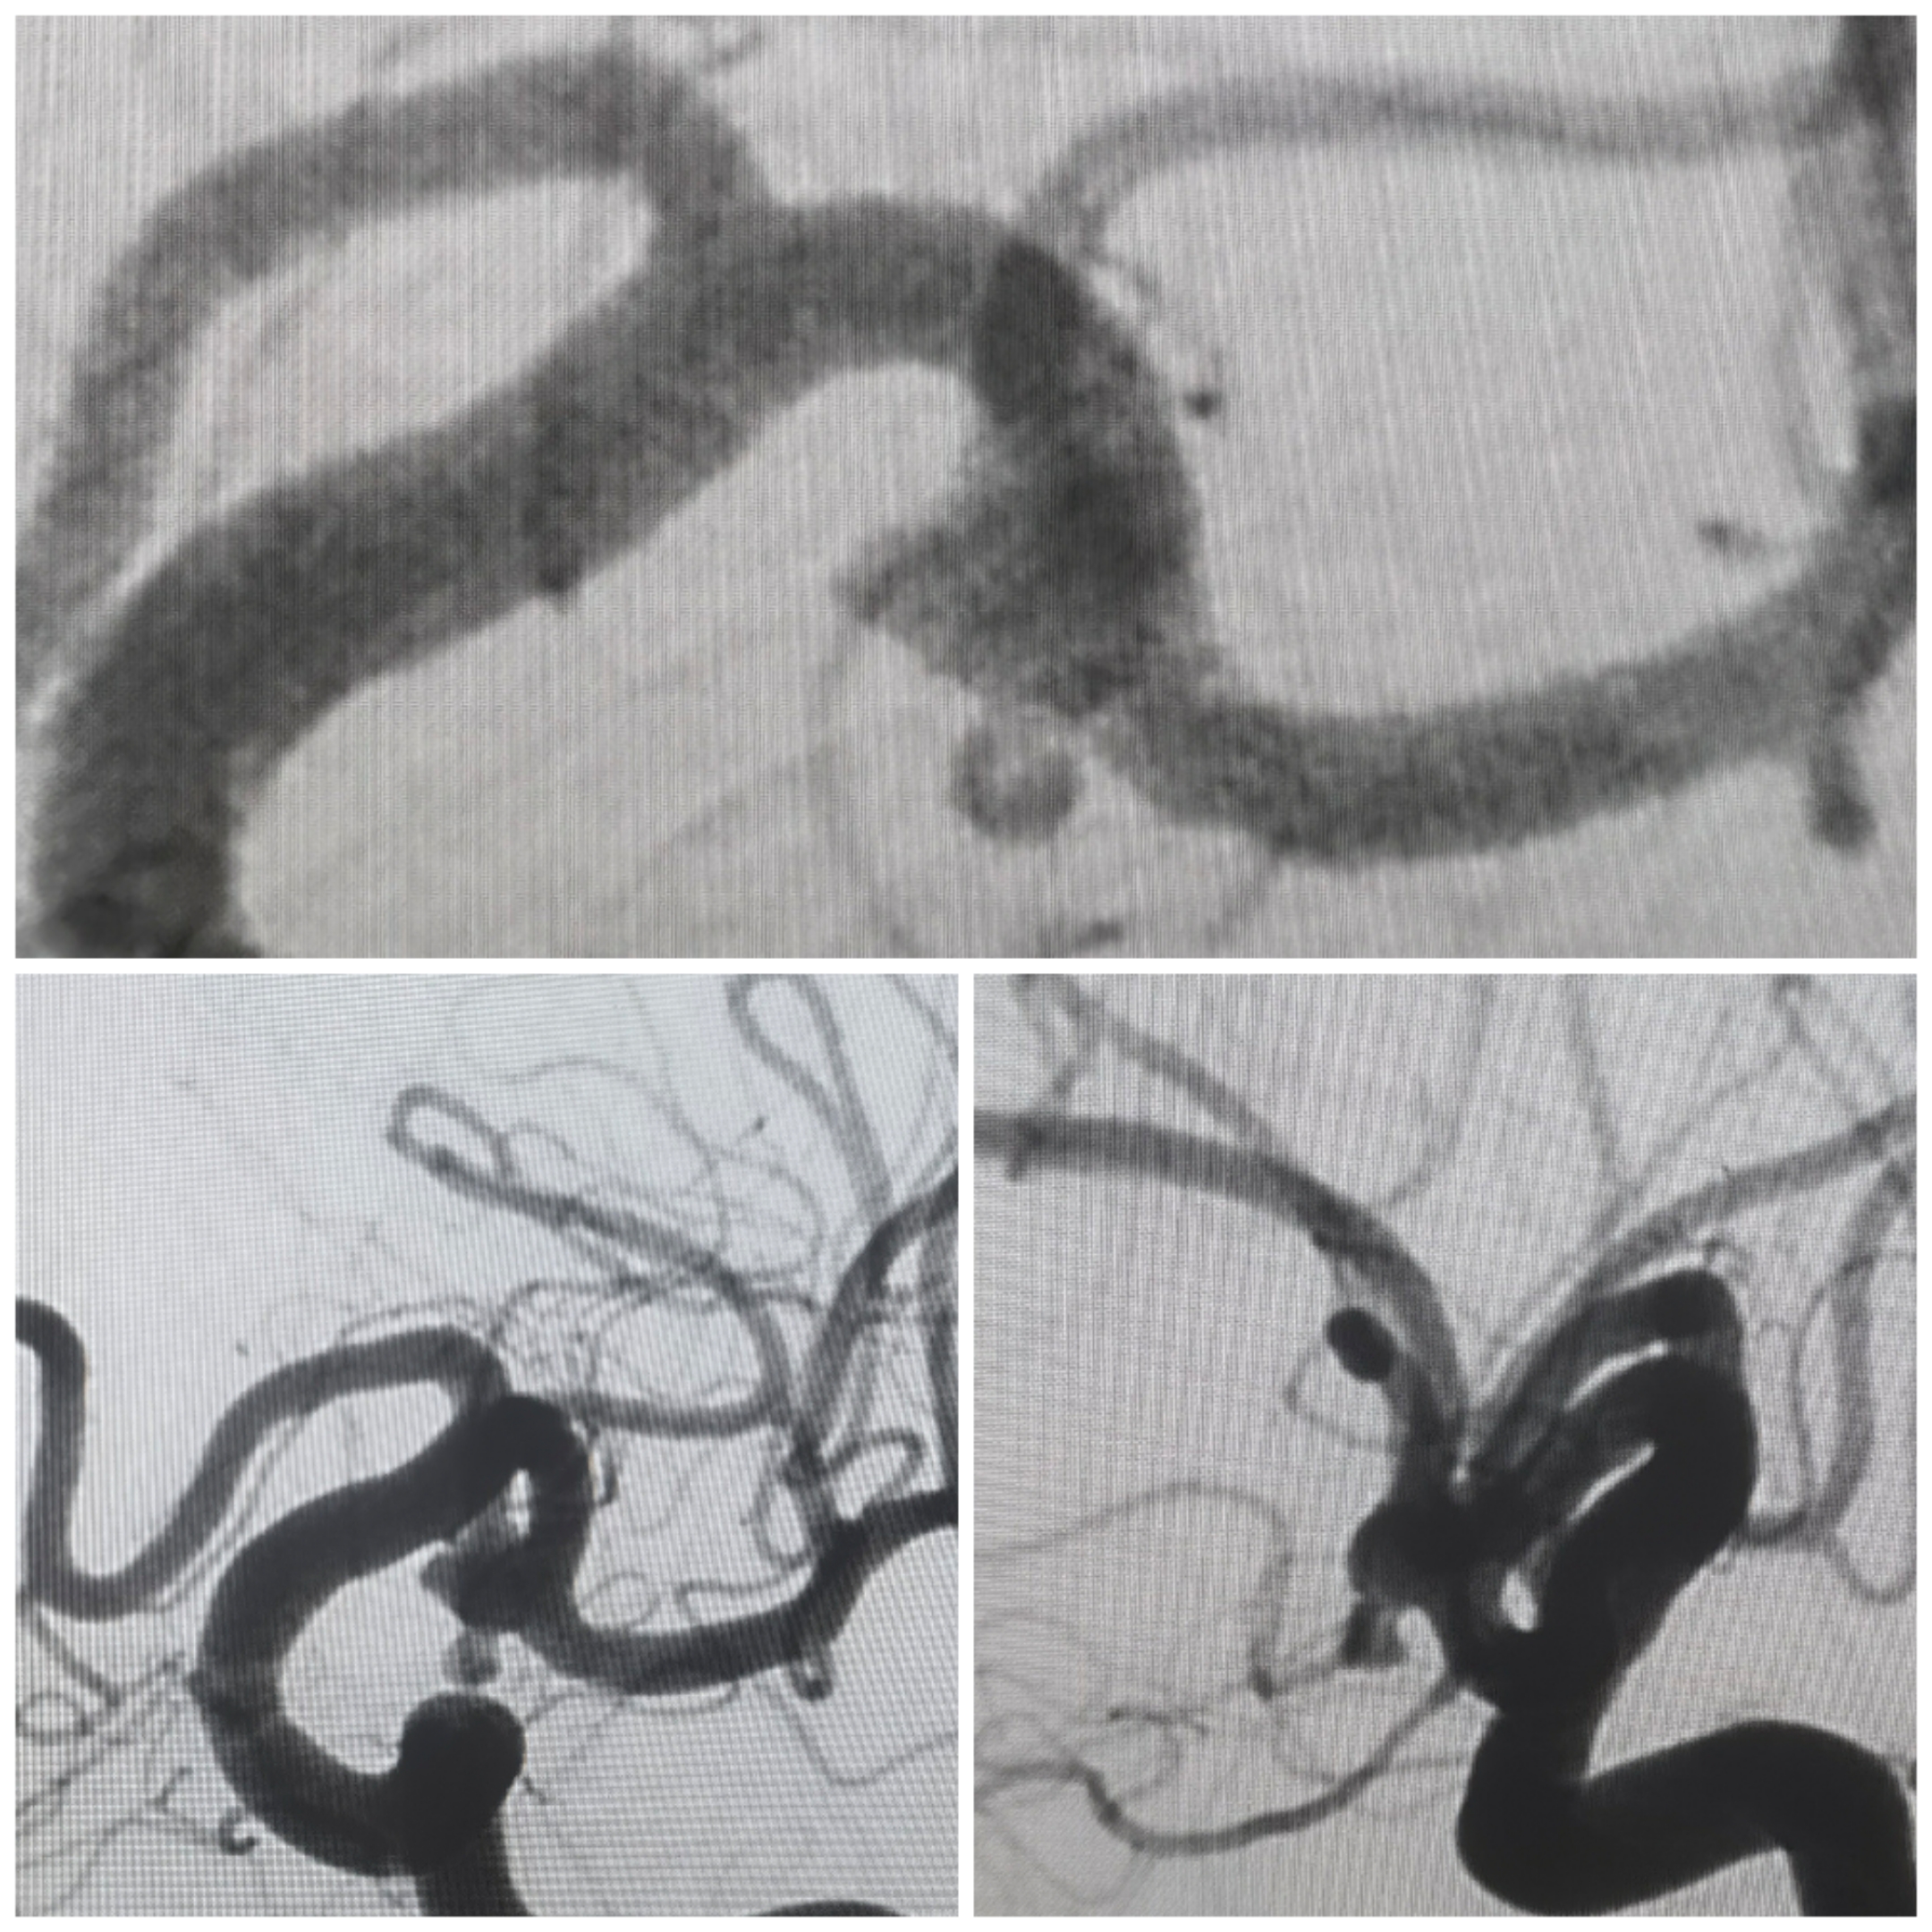

病例2大脑中分叉分叶动脉瘤

SAH入院,Hunt-Hess分级2级,

术前CTA:右侧大脑中分叉部动脉瘤

术前造影3D重建

术前计划:支架导管释放至上干,应用开环支架穹窿效应保护下干,双微导管分区栓塞

拟支架释放角度

栓塞过程

栓塞术后情况

栓塞术后3D重建